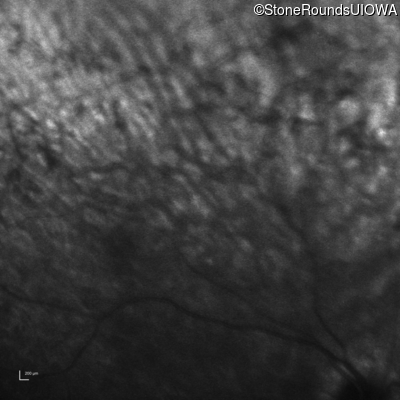

Infrared Fundus Photograph - Right - Hand Motion sc

Exemplar